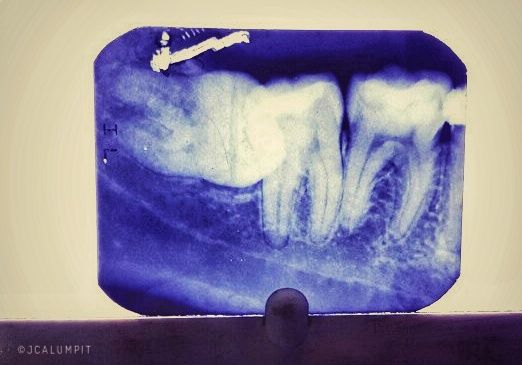

I have assisted two of my dental co-clinician on their special surgery cases today. The first one was Aza's odontectomy case. A lower third molar impaction. The case was a Horizontal impaction, depth A (which means it is above the cervical line of the 2nd molar), and ramus relationship is Class 1. The way to get the tooth out is to get a clear access to the area by doing a flap. Once a flap is done, bone reduction with a bone bur is done. A vertical cut with a straight fissure bur is used to section the tooth in half. So the mission is to cut the tooth into two parts. The first part would be the crown of the tooth which we see if we smile and the second part would be the root which is below the gums. After the crown is removed, we would now try to luxate (wiggle to loosen and try to dislocate the tooth from the socket) the tooth. A dental forcep (pincers or tweezers used in dental surgery) is used to removed the tooth from the socket. It may sound scary but it is very simple once you get to know how to use it.

A dental xray of a horizontal impacted third/wisdom tooth

The time it take to do this procedure depends on how difficult the case is and how experienced the clinician is. We tend to not say how long the procedure will take because if we tell our patient a certain time, they might complain later on if we didn't hit the target given. Just know that every case is different and we will never have the same one.

The tooth was divided into two parts